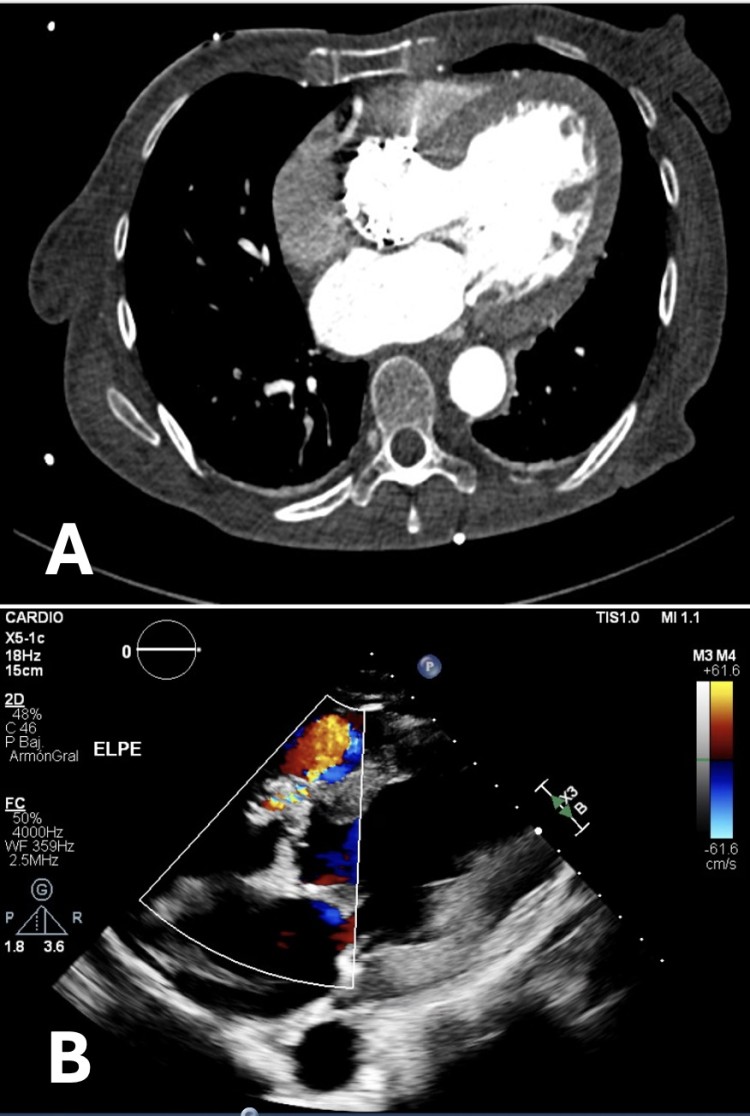

AngioTC sincronizado (A) y ecocardiograma transtorácico en plano paraesternal eje largo (B) en el que se visualiza fístula entre raíz aórtica y ventrículo derecho.